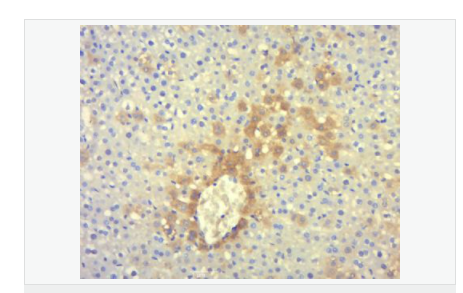

交叉反應(yīng):Human,Mouse,Rat(predicted:Dog,Pig,Cow,Rabbit,GuineaPig) 推薦應(yīng)用:IHC-P,IHC-F,IF,Flow-Cyt,ELISA

| 產(chǎn)品應(yīng)用 | ELISA=1:5000-10000 IHC-P=1:100-500 IHC-F=1:100-500 Flow-Cyt=1ug/Test IF=1:100-500 (石蠟切片需做抗原修復(fù)) not yet tested in other applications. optimal dilutions/concentrations should be determined by the end user. |